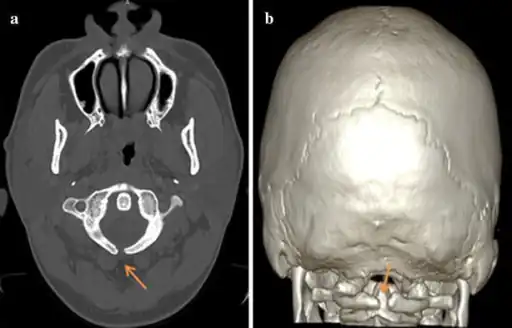

a,b) Atlas spina-bifida oculta

a,b) Atlas spina-bifida oculta Three-dimensional ultrasound image of the fetal spine at 21 weeks of pregnancy